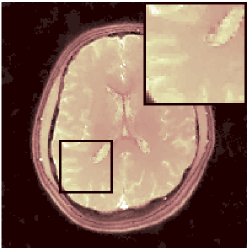

VI-F MRFResnet’s consistency with DM

Further to section VI-C validations, we compare parametric maps computed by DM and MRFResnet for the in-vitro and in-vivo scans, where the LRTV algorithm was applied for TSMI reconstruction. Results are summarised in Table III and for the in-vivo 2D spiral scan is illustrated in Figure 9. We observe very small differences in parametric maps (Table III) and particularly for the regions corresponding to white and grey matters predictions are highly consistent with each other (Figure 9).

. diff T1(s) diff T2 (s) diff PD (a.u.)